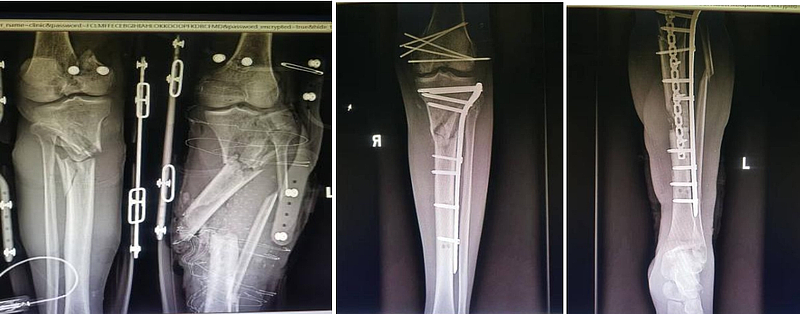

手术室中,无影灯亮起,一场关乎生死的手术正式开始。手足外科团队凭借着精湛的技术和丰富的经验,在患者的伤处精心操作。清创、固定骨折、修复屈伸肌腱、探查血管神经、吻合血管神经……每一个步骤都精准无误,每一个动作都紧密衔接,容不得半点马虎。在漫长而又紧张的数小时里,团队成员们全神贯注、不懈努力,汗水湿透了他们的手术服,却丝毫没有动摇他们的决心。终于,手术顺利完成。术后患者的患肢及皮瓣均成功存活。